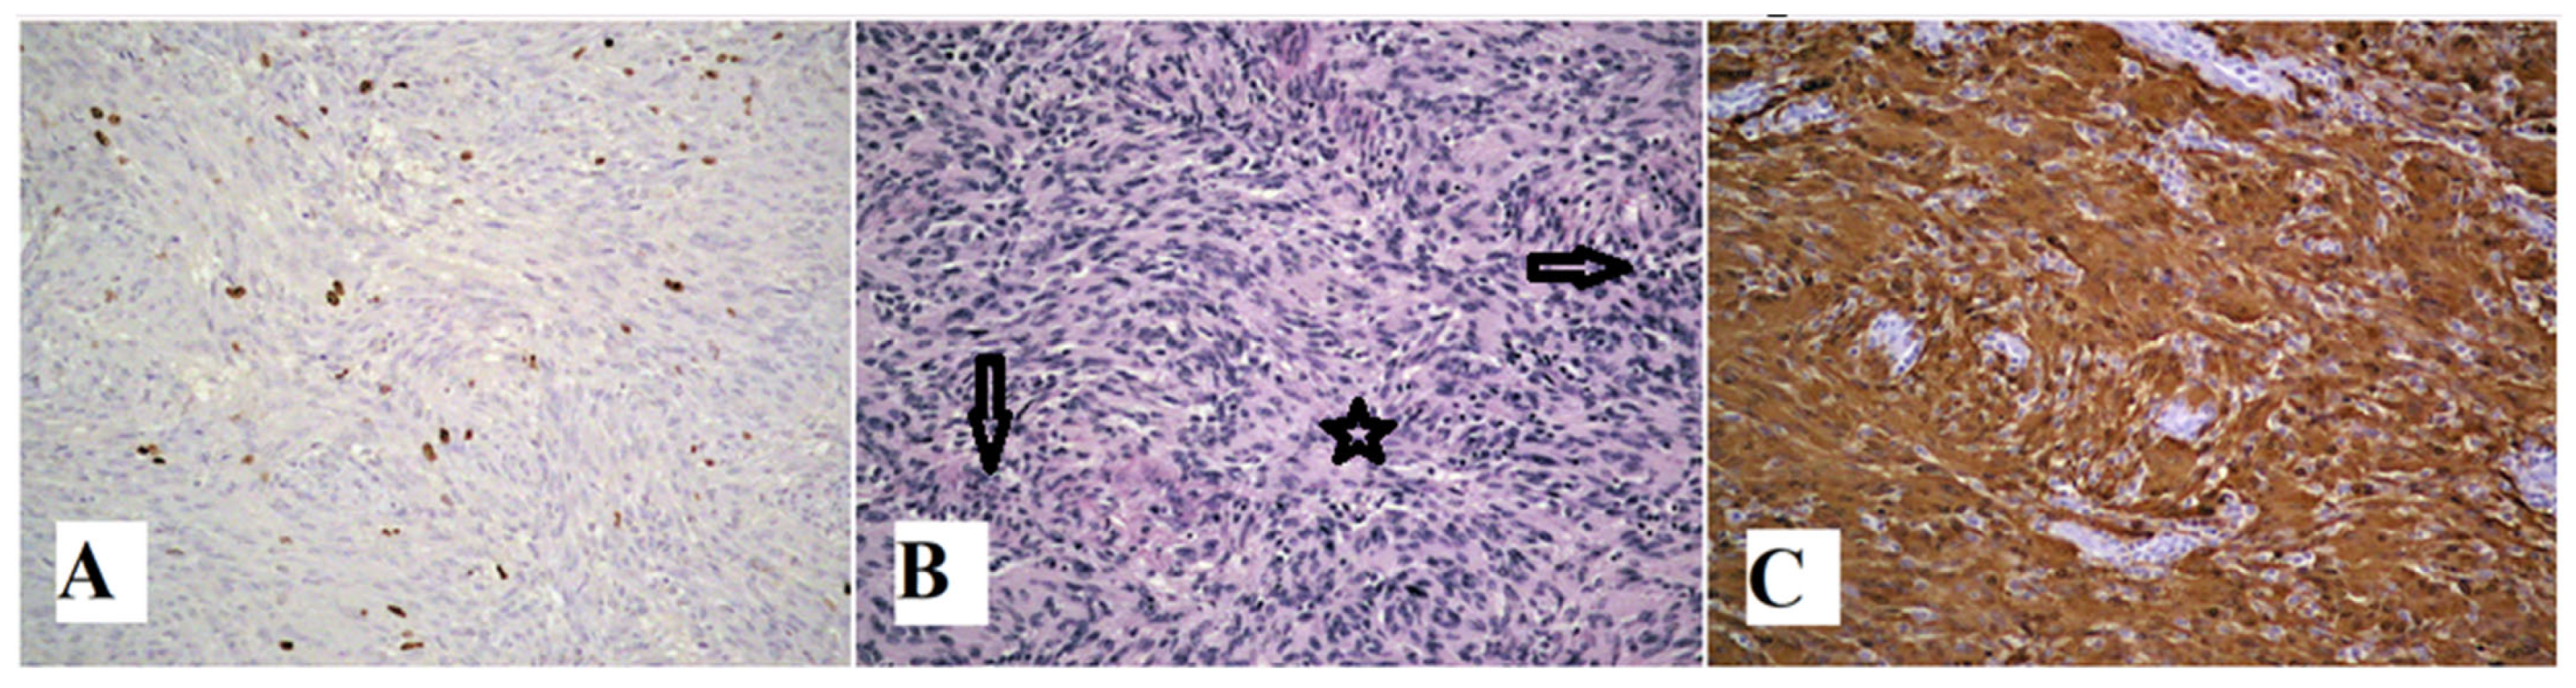

2. Case Report